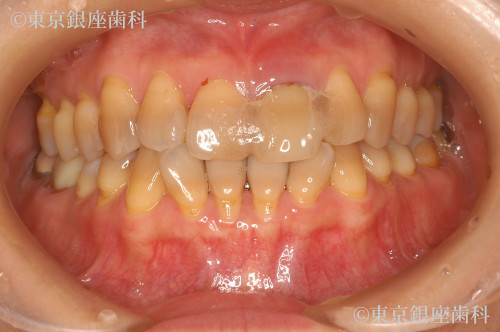

前歯の抜歯即時埋入イミディエートの症例

Before

疾患 前歯の欠損

施術内容 抜歯即時埋入イミディエート

治療期間 7カ月 費用 62万円(税込)

治療期間 7カ月

費用 62万円(税込)

根破折により抜歯即時埋入、イミディエート